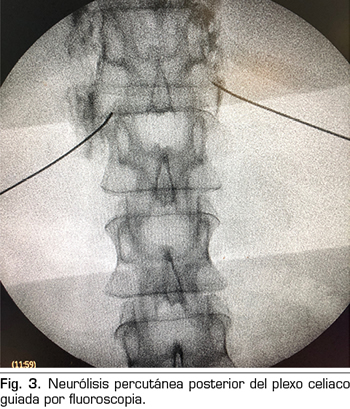

– Abordaje transcrural: el más utilizado para el bloqueo del plexo celiaco (Figura 3). El paciente se coloca en decúbito prono, identificando el cuerpo vertebral L1 y avanzando una aguja por cada lado, a unos 7,5 cm de la línea media, hasta atravesar la crura diafragmática y bloquear el plexo.

Consiste en la destrucción de las fibras que componen el plexo celiaco mediante la inyección de un agente neurolítico, prefiriéndose el uso de alcohol debido a su menor afinidad por los vasos sanguíneos, comparado con el fenol. El abordaje clásico más utilizado es el transcrural bilateral por vía posterior, guiado por fluoroscopia o TAC.

En los últimos años han surgido varios ensayos controlados y aleatorizados que han sido analizados en una revisión sistemática posterior por Mercadante y cols. (17), demostrando una mayor eficacia analgésica de manera significativa, aunque mínima, en los grupos en los que se realizó la neurólisis del plexo celiaco comparado con los grupos tratados con opioides sistémicos. Además, demostraron una reducción en el consumo de opioides en la mayoría de trabajos (18-29) y una mejoría en la calidad de vida en algunos de ellos (20,27,29). Las complicaciones eran raras en todos los abordajes, aunque no era una variable primaria en ningún estudio. A pesar de estos resultados, la calidad de todos los trabajos, exceptuando dos (24,28), era pobre debido a limitaciones importantes como el tamaño muestral, la ocultación de la asignación o el tiempo de evaluación de la eficacia del bloqueo.

Se han publicado complicaciones derivadas de la neurólisis del plexo celiaco, siendo infrecuentes en la mayoría de casos (30). Hay que saber diferenciar los efectos adversos esperados de la simpatectomía química de las complicaciones derivadas de la técnica. Un 20-42 % de pacientes presentan hipotensión debido a la vasodilatación secundaria a la neurólisis. La diarrea tiene una incidencia del 10-25 %, resolviéndose en las primeras 48-72 horas. La presencia de dolor lumbar tiene una incidencia que va del 5 % al 60 % según las series. También está descrita la omalgia en un 1 % de casos, debido a la irritación diafragmática. Con respecto al abordaje percutáneo, las complicaciones de la técnica son raras (2 %), estando descritos el déficit neurológico (debilidad y parestesias), la gastritis hemorrágica, la duodenitis, el neumotórax, la hematuria y la muerte (3,1 %). La paraplejia está publicada con los abordajes posteriores (0,15 %), pudiendo ser debida a la lesión directa de la aguja en la médula espinal o al infarto espinal secundario a un espasmo arterial.